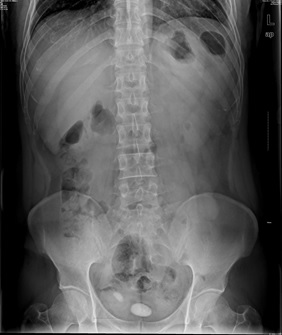

05卷-4.男,55岁,反复尿频、尿痛、排尿困难半年(本题满分2.00分)

膀胱结石

本题答案:B

题目解析:【该题针对“X线-泌尿系结石”知识点进行考核】